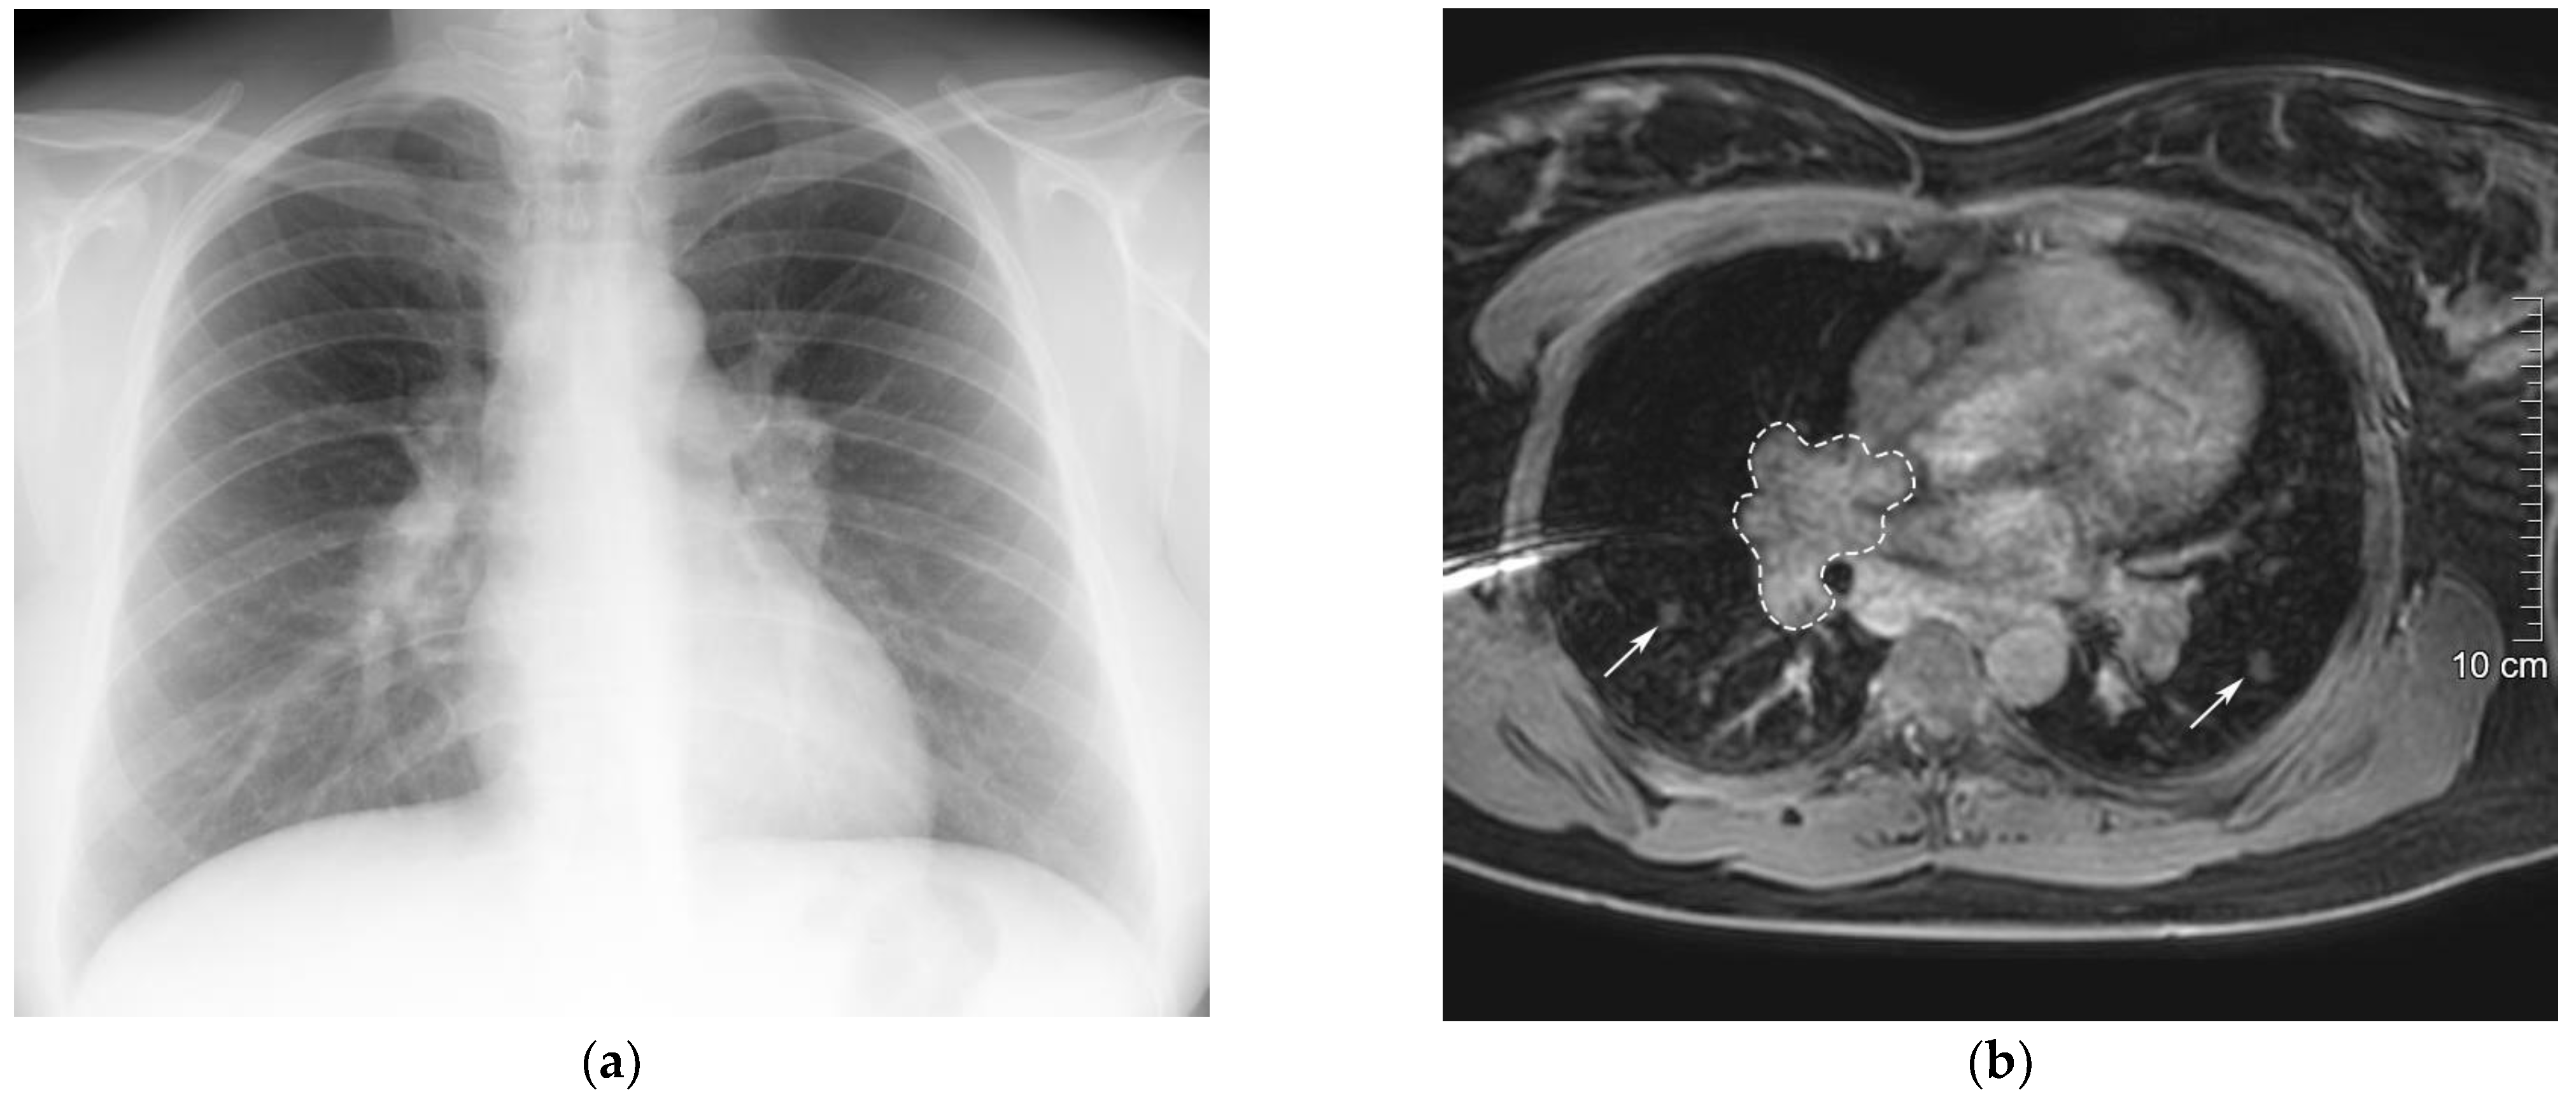

The patient’s first symptoms began 3 years ago, when she started complaining of general weakness, fatigue, and shortness of breath during moderate physical activity. A chest X-ray and computed tomography (CT) scan were performed and revealed hilar and mediastinal lymphadenopathy (Figure 2a). Considering the patient‘s symptoms and radiological findings, she was referred to a pulmonologist. Pulmonary function testing, including spirometry and lung diffusion test, was performed and no abnormalities were detected. Magnetic resonance imaging (MRI) of the neck, chest, abdomen, and pelvis was performed to specify the CT scan findings and differentiate granulomatous disease from lymphoproliferative disorders. MRI confirmed the presence of mediastinal lymphadenopathy and demonstrated small perilymphatic nodules in the perihilar region of the lungs, both of which accumulated contrast agent (Figure 2b). Moreover, hepatosplenomegaly was observed and suspected to be caused by sarcoidosis. To confirm the diagnosis by pathology, a perihilar lymph node biopsy was attempted. However, the biopsy was performed inaccurately and the results were not informative. Therefore, based on the MRI scan results, the final clinical diagnosis of mediastinal and pulmonary sarcoidosis was made. After a year, MRI of the chest was repeated and did not show any new lesions in the lungs or lymph nodes. Considering the stable course and mild symptoms of the disease, no treatment was prescribed and the patient was kept under observation.

Figure 2.

Radiological examinations of the patient’s chest. (a) Chest X-ray showing mediastinal lymphadenopathy. (b) Chest MRI showing gadolinium-enhanced pulmonary nodules (arrows) and mediastinal lymphadenopathy (dashed line) in mDIXON-W MRI sequence 5 min after gadolinium injection.